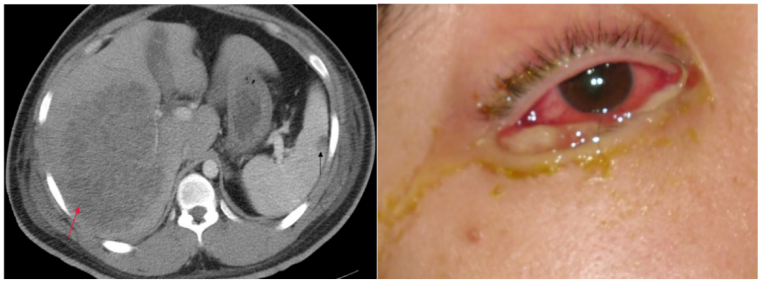

动物模型是鉴定hvKP菌株的方法之一,通过给小鼠接种不同浓度的KP或计算蜡蛾幼虫的半数致死量来确定细菌毒力。但实验周期较长,操作复杂,不适合应用于临床,因此需要进一步研究和改进。高黏性是hvKP最重要的特点之一。既往很多实验室依据拉丝试验鉴别hvKP,但拉丝试验阳性并不代表KP高毒力,因为细菌的高黏性与高毒力有一定相关性,但非必要条件。多位点序列分型和荚膜抗原血清型曾用于鉴别hvKP,某些特殊的序列型(如ST23、ST65和ST86)以及荚膜血清型(如K1和K2)与hvKP密切相关,尤其是ST23型与hvKP所致肝脓肿明显相关。随着二代测序技术的发展,一些毒力质粒上的特殊基因,如peg-344、iroBCDN、iucABCD、iutA、prmpA、pks等被认为是当前实验室鉴别hvKP的最佳标志物。另外一个判断hvKP的独立因子是铁载体,因为铁元素是细菌生长繁殖不可或缺的微量元素。KP主要通过铁载体来获取铁元素,其主要有4种铁载体,包括肠杆菌素、沙门菌素、耶尔森杆菌素和需氧菌素,其中肠杆菌素在cKP和hvKP中差异不大,而其他3种铁载体在hvKP中明显多于cKP。KP是多重耐药细菌中最常见的一种,其中耐碳青霉烯类肺炎克雷伯菌(CRKP)占比超过20%。近年来有关hvKP耐药菌株的报道越来越多,更严重的是,大多数MDR-hvKP的报道都来自亚洲,特别是我国。我国分离自侵袭性感染的hvKP菌株中检出12.6%产超广谱β-内酰胺酶,ST11型CRKP中高毒力株检出率约为30%。耐药原因方面,耐碳青霉烯类高毒力肺炎克雷伯菌(CR-hvKP)的耐药原因与CRKP基本一致,包括碳青霉烯酶的合成、外膜孔蛋白的下调或缺失、外排泵系统的激活以及生物膜成分的改变。高毒力及高耐药的双重表型使得CR-hvKP的临床表现多样而复杂,这也使得临床治疗更加棘手,给患者带来的危害也更加严重。目前认为hvKP入侵或感染的主要方式与cKP类似。cKP的入侵方式比较明确, 如会阴部的定植菌可逆行导致泌尿系感染, 肠道内的定植菌可以因肠道破裂进入腹膜腔而造成腹膜炎, 口咽部定植菌可通过误吸进入肺组织引发肺炎。hvKP感染的先决条件是前期的暴露、获得与定植, 但并非所有的细菌定植均会发展为感染。有关hvKP入侵机制的分析多源于既往对cKP的认识, hvKP比cKP更易引发肝脓肿等侵袭性感染。KP在肠道、鼻咽部以及腋窝等部位均可定植, 其中消化道是其最主要的定植部位, 且不同地区的定植率差异较大, 从20%到85%不等。hvKP引起细菌性肝脓肿等侵袭性感染的比率相较于cKP更高, 肠道内定植的hvKP突破肠黏膜并通过门脉系统入侵肝脏是一种合理的解释, 但hvKP通常感染健康宿主。研究者推断, 黏膜上皮的隐匿性破坏、细菌定植数量的增加以及宿主的基因差异在hvKP入侵过程中可能发挥了作用。hvKP感染后菌株的生长与生存以及进一步侵袭与其自身强大的抗吞噬作用和繁殖能力有关。hvKP菌株比cKP菌株更能抵抗吞噬作用、中性粒细胞和补体介导的活性,以及中性粒细胞细胞外陷阱(NET)。此外,与cKP菌株相比,hvKP菌株在体外人体体液中更易繁殖,并且在多种感染模型中毒力更强。hvKP菌株比cKP菌株更易发生多部位感染和/或转移性传播,通常通过血流引起多部位的侵袭性感染。hvKP感染常导致脓肿形成,涉及多种器官系统,如肝、眼、脑等,症状严重,病死率高。图1直观地展示了hvKP引起的原发性和转移性感染的常见部位,包括脑膜炎/硬膜下脓肿、眼内膜炎、肺部感染、脓毒血症、肝/脾脓肿、泌尿系感染、肾脏/肾周软组织感染、坏死性筋膜炎、化脓性关节炎等,这些都是hvKP容易引发的感染及部位。图1 CR-hvKP引起的原发性和转移性感染的常见部位图源:Sci Bull (Beijing), 2023, 68(21):2658-2670.(1)hvKP所致肝脓肿:社区获得性化脓性肝脓肿由hvKP所致,常为单一病原体感染,且多伴有其他器官系统感染。(2)hvKP菌血症性社区获得性肺炎(CAP):hvKP所致的菌血症性CAP临床表现较重,病死率高达55%以上,多器官功能衰竭发生率高。(3)hvKP所致眼内炎:眼内炎由hvKP引发,组织损伤迅速,静脉抗菌治疗联合玻璃体内抗菌药物注射后仍有一定比例患者摘除眼球。(4)hvKP中枢神经系统感染: hvKP引发的社区获得性脑膜炎导致的感染性休克病死率较高, 脑脓肿、硬膜下脓肿和硬膜外脓肿也有发生。(5)hvKP泌尿系感染:hvKP可通过血流播散至肾脏、肾周以及前列腺等部位,引发泌尿系感染。(6)hvKP所致坏死性筋膜炎:骨骼肌肉及软组织感染,如髂窝脓肿、深部颈间隙感染、骨髓炎、化脓性关节炎等也可能与hvKP有关。图2所示分别为hvKP所致肝脓肿并转移扩散至脾,以及hvKP所致眼内炎。两名患者既往均体健。图源:Clin Microbiol Rev, 2019, 32(3):e00001-19.肝脓肿是高度怀疑hvKP感染的临床表现之一,伴有眼内炎、血流感染、脑膜炎、脾脓肿、骨髓炎和坏死性筋膜炎等。眼内炎也是高度怀疑hvKP感染的临床表现,由于组织损伤迅速,即使接受静脉抗菌治疗并配合玻璃体内的抗菌药物注射。此外,脑膜炎、脾脓肿、骨髓炎和坏死性筋膜炎等也要高度怀疑hvKP感染,其导致的感染性休克患者的住院病死率较高。hvKP可以通过血流播散至肾脏、肾周以及前列腺等部位,引起泌尿系感染,导致肾周脓肿、前列腺炎等。坏死性筋膜炎是一种严重的骨骼肌肉及软组织感染,与hvKP有关,其他还包括髂窝脓肿、深部颈间隙感染等。送检合适的样本种类,留取合格的、有高诊断价值的临床样本,建议采集病灶脓液、穿刺液等样本,排除正常菌群和定植菌的干扰。样本采集时间最好是病程早期或急性期,尽可能在抗菌药物使用前采集临床样本,以确保样本的代表性和诊断准确性。(1)拉丝试验:拉丝试验是确认hvKP生物学活性(毒力)的方法之一,通过观察小鼠接种不同浓度KP或计算蜡蛾幼虫的半数致死量来确定细菌毒力。(2)荚膜分型:荚膜分型也是确认hvKP生物学活性(毒力)的方法,根据K抗原不同将KP分成82个血清型,K1和K2是hvKP的主要型别。(3)铁载体检测:铁载体检测有助于确认hvKP的生物学活性,铁载体是细菌分泌的一种低分子量铁螯合剂,能够辅助细菌从外环境中摄取铁元素。(4)毒力表型检测:毒力表型检测包括肠杆菌素、沙门菌素、耶尔森杆菌素和需氧菌素等4种铁载体的检测,用于鉴别hvKP和cKP。(5)NGS检测: NGS是一种先进的分子生物学技术, 通过测定基因组或转录组的序列来评估细菌的毒力, 适用于确认hvKP的生物学活性。图源:中华检验医学杂志, 2023, 46(11):1164-1172.hvKP感染的治疗遵循4个基本原则:①及时的经验性抗感染治疗:在药敏结果出来前,临床应及时进行经验性用药,将减少后续感染扩散风险。②正确的给药方式:依据药效学/药代动力学给予正确的给药方式,以确保药物能够充分发挥作用。③恰当的抗菌方案:根据药敏试验结果选择恰当的抗菌方案,以确保治疗的有效性。④局部脓肿引流:及时对局部脓肿进行引流,以减轻症状并加速愈合。在药敏结果出来前,临床应及时进行经验性用药,将减少后续感染(如眼内炎)扩散风险。目前已知hvKP对碳青霉烯类抗生素最易耐药。在一组65株碳青霉烯类耐药hvKP菌株的体外试验中,hvKP菌株对头孢他啶-阿维巴坦、多黏菌素和替加环素都敏感。根据现有的药敏试验,对于中枢神经系统感染,可选用头孢曲松和美罗培南;对于前列腺感染,氟喹诺酮类药物、三甲氧苄啶-磺胺甲噁唑或磷霉素可达到治疗效果;对于眼部感染,可选用全身治疗和玻璃体内治疗的结合。hvKP导致肝脓肿最常见,但几乎所有器官和解剖位置都有脓肿发生可能。对于关键器官的脓肿或破裂的脓肿,需要立即考虑手术治疗。非关键部位的大范围脓肿最好通过经皮穿刺置管引流可及性优先,保留手术干预用于经皮穿刺置管引流失败情况。由于hvKP感染的脓肿液通常是黏稠的,引流术中经常并发导管堵塞,因此可行时应使用最大孔径引流管,并尽量经常冲洗以防止导管堵塞。针对较小的脓肿(<5 cm),单用抗生素治疗有可能治愈。利用其他辅助检查手段(如影像学检查)评估患者对治疗的反应并确定治疗的持续时间。